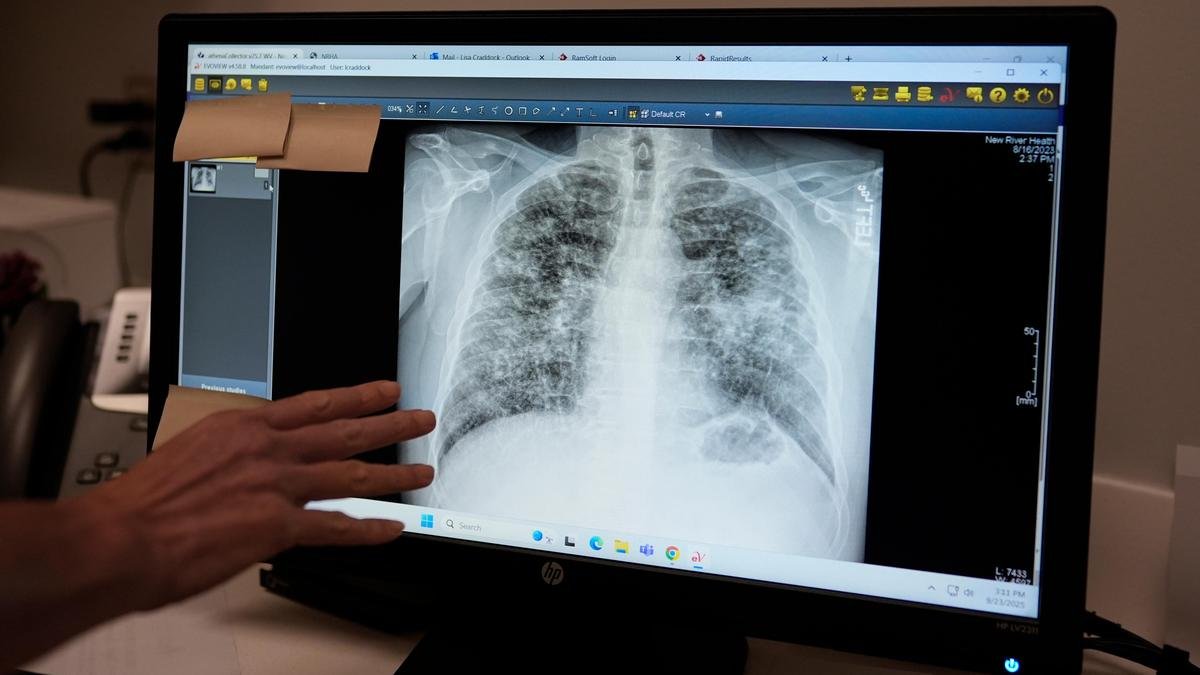

खराब वायु गुणवत्ता तत्काल जलन और अस्थमा, सीओपीडी और फेफड़ों के कैंसर जैसी दीर्घकालिक स्थितियों का कारण…